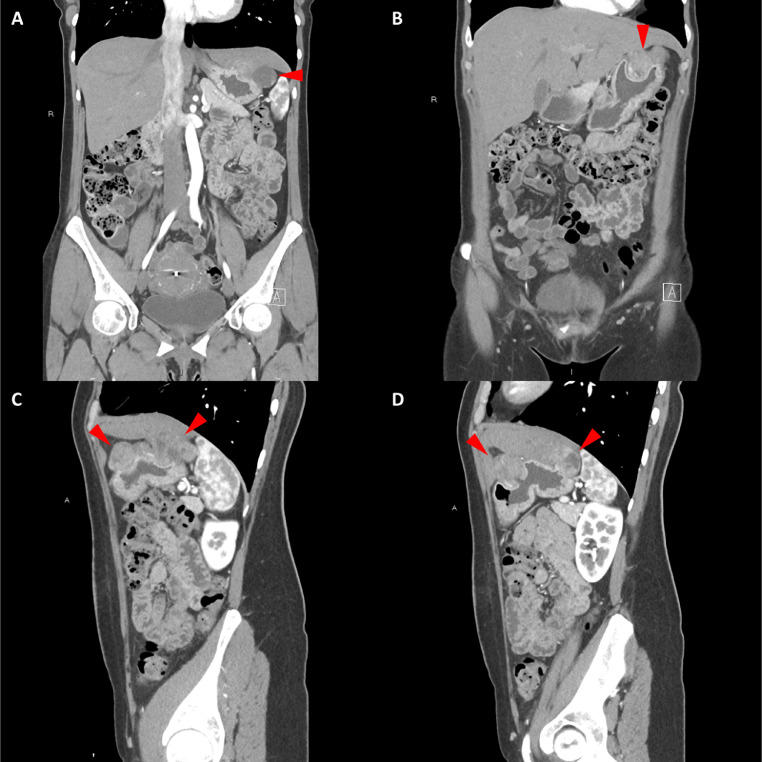

胸部、腹部和骨盆的對比增強(qiáng)動脈和靜脈期 CT 顯示多個(gè)圓形、主要是血管豐富的異質(zhì)腫塊,具有囊性和實(shí)性成分,起源于胃底和胃體(圖 2-4)。 病變部分呈外生結(jié)構(gòu),被認(rèn)為位于粘膜下層。 在頸部多發(fā)同步性副神經(jīng)節(jié)瘤的情況下,賊初的鑒別診斷包括多發(fā)性副神經(jīng)節(jié)瘤、多發(fā)性 GIST 以及轉(zhuǎn)移性疾病。

Fig. 3

圖 3:多個(gè)胃腸道間質(zhì)瘤的冠狀和矢狀圖像。 (A 和 B)冠狀動脈相對比增強(qiáng) CT 圖像顯示胃賁門產(chǎn)生的外生性腫塊。 (C 和 D)矢狀動脈相位對比增強(qiáng)圖像顯示腫塊的異質(zhì)性和外生結(jié)構(gòu)。